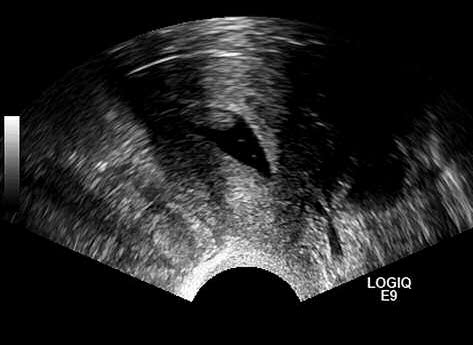

Соногистерография проводится путем введения физиологического раствора в полость матки, что позволяет лучше оценить состояние полости и выявить внутриполостные образования. Чувствительность соногистерографии для выявления патологии эндометрия у пациенток с ПМК составляет 86,5% (95% ДИ 63,6–100%), специфичность – 91,1% (95% ДИ 63,2–100%); рис. 3 [32].

Рис. 3. Пациентка М., 60 лет, постменопауза 10 лет. Эпизод кровянистых выделений из половых путей. При ТВ УЗИ эндометрий визуализируется неотчетливо, при соногистерографии – полип эндометрия (собственные данные).